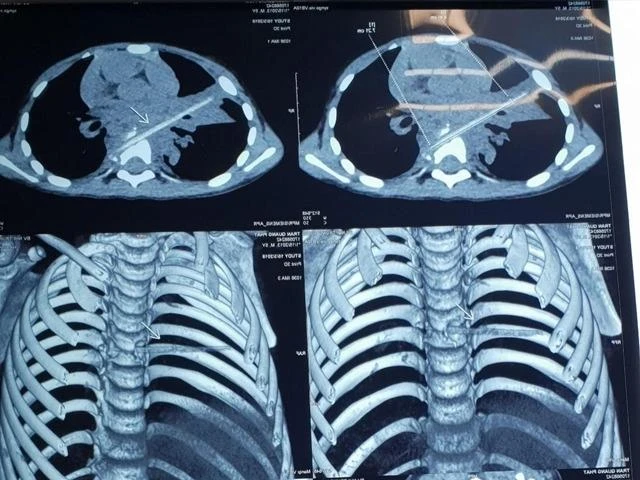

Hình ảnh que nứa trong phổi bệnh nhi. Ảnh: BVCC

Hình ảnh chụp vi tính cắt lớp sau đó cho thấy bệnh nhi có một dị vật dài nhọn kích thước 72x4 mm tại vị trí nhu mô thùy phổi ở thùy giữa phổi phải. Dị vật này đi từ trước ra sau, xuyên qua khe giữa hai thân đốt sống 6, 7 và làm vỡ thân đốt sống. Khi nằm lại trong cơ thể, dị vật gây phản ứng thâm nhiễm viêm trung thất sau quanh đốt sống 6, 7. Đây cũng là nguyên nhân khiến bé M. phải vào viện điều trị viêm phổi trong suốt tám tháng.